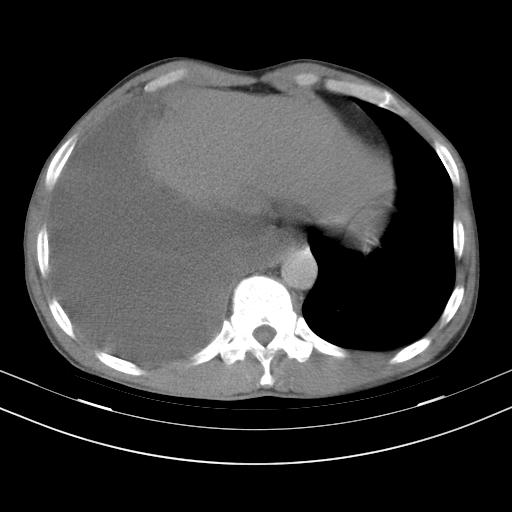

男性,44岁,结核病史多年。现胸闷气短,咳嗽,偶咳血。

右侧胸腔积液

右肺下叶不张

双肺多发结节影最分空洞形成考虑占位不除外结核

双肺陈旧性病变

1、右侧大量胸腔积液伴右肺压缩性膨胀不全,建议抽液治疗后复查 2、两肺继发性tb伴空洞形成。

1)两肺继发性肺结核伴空洞形成,左肺多发性结核球。2)右侧大量胸腔积液伴右肺部分膨胀不全。3)纵隔淋巴结肿大。

1,双肺多发结节 并空洞影改变, 左侧胸腔积液并部分包裹, 结合原病史首先考虑结核. 但也不除外其它.

2,左侧有一根肋骨陈旧性骨折? 建议追查 .